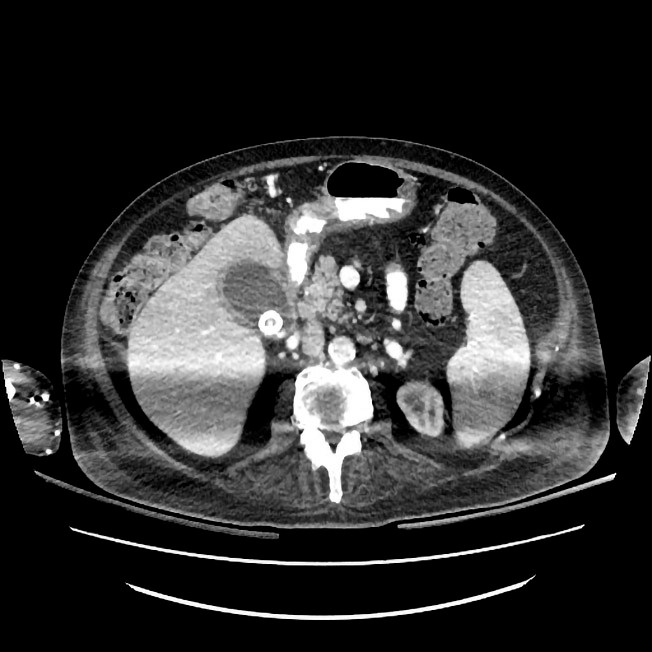

To måneder etter skaden ble pasienten på ny febril. Ved undersøkelse var han ikke orientert for tid. Han var ikke nakkestiv. Respiratorisk og sirkulatorisk var han uendret. Blodprøver viste CRP 91 mg/l, leukocytter 10,3 ∙ 109/l og nøytrofile granulocytter 7,5 ∙ 109/l. Urinstiks fra kateter viste utslag på leukocytter, nitritt og blod, og det ble startet peroral antibiotikabehandling mot antatt urinveisinfeksjon (trimetoprim-sulfametoksazol 160 mg/800 mg × 2). Blodprøver neste dag viste raskt stigende CRP på 219–261 mg/l. Undersøkelse av hjertet, lungene og abdomen viste igjen normale funn, bortsett fra at abdomen var utspilt og diffust trykkømt, men uten fokal trykkømhet, reflektorisk stramming eller bankeømhet over nyrelosjer. På mistanke om øvre urinveisinfeksjon ble det besluttet å bytte til intravenøs antibiotikabehandling (cefotaksim 2 g × 3). For å utelukke ny pneumoni ble det tatt røntgen thorax, som var normalt. Pasienten fremsto neste døgn økende delirisk med fallerende allmenntilstand. Vitale parametre var uendrete. Det var stigende CRP til 328 mg/l og forhøyete verdier av leukocytter på 13 ∙ 109/l og nøytrofile granulocytter på 10,4 ∙ 109/l. Verdiene av ALP, ASAT, GT og kreatinin var innenfor referanseområdet, mens bilirubin var lett forhøyet på 23 µmol/l (< 19 µmol/l). Mannen klaget over brennende smerter i alle ekstremiteter. Han hadde hatt tregere avføring enn vanlig, og det var synlig økt bukomfang, men uendrete funn ved undersøkelse av abdomen. Etter diskusjon i kollegiet valgte man nå å be om et umiddelbart kirurgisk tilsyn på grunn av mistanke om akutt abdomen. Kirurgisk vakthavende fant lett trykkømhet ved dyp palpasjon under høyre kostalbue og utspilt abdomen, men ingen kliniske tegn til peritonitt. Dette var nokså sparsomme kliniske funn, men man valgte å henvise pasienten til CT abdomen på mistanke om abdominalt infeksjonsfokus, spesielt i galleveier. CT-undersøkelsen viste galleblære med gallesten og fortykket vegg forenlig med galleblærebetennelse (figur 2). Det ble startet behandling av galleblærebetennelsen med piperacillin/tazobaktam intravenøst samt perkutan drenasje via galleblæredren, hvor det tømte seg gult puss. Behandlingen ga rask klinisk og laboratoriemessig bedring.